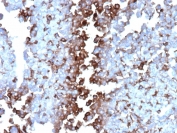

IHC staining of FFPE human adrenal gland tissue with Apolipoprotein J antibody (clone CLU/4737). Inset: PBS used in place of primary Ab (secondary Ab negative control). HIER: boil tissue sections in pH 9 10mM Tris with 1mM EDTA for 20 min and allow to cool before testing.